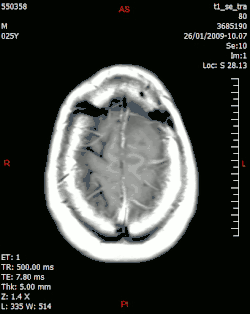

Физика медицинской визуализации также известна как физика диагностической и интервенционной радиологии. Клинические (как «штатные», так и «консультирующие») физики[14] обычно занимаются областями тестирования, оптимизации и обеспечения качества таких областей физики диагностической радиологии, как рентгенография, рентгеноскопия, маммография, ангиография и компьютерная томография. , а также методы неионизирующего излучения, такие как УЗИ и МРТ. Они также могут заниматься вопросами радиационной защиты, такими как дозиметрия (для персонала и пациентов). Кроме того, многие физики-визуалисты часто также связаны с системами ядерной медицины, включая однофотонную эмиссионную компьютерную томографию (ОФЭКТ) и позитронно-эмиссионную томографию (ПЭТ). Иногда физики-визуалисты могут заниматься клиническими областями, но в исследовательских и учебных целях[15], например, для количественной оценки внутрисосудистого ультразвука как возможного метода визуализации конкретного сосудистого объекта. В некоторых случаях для научных исследований и диагностики структур и функций на микро- нано-уровне целесообразно использование электронной микроскопии[16][17].